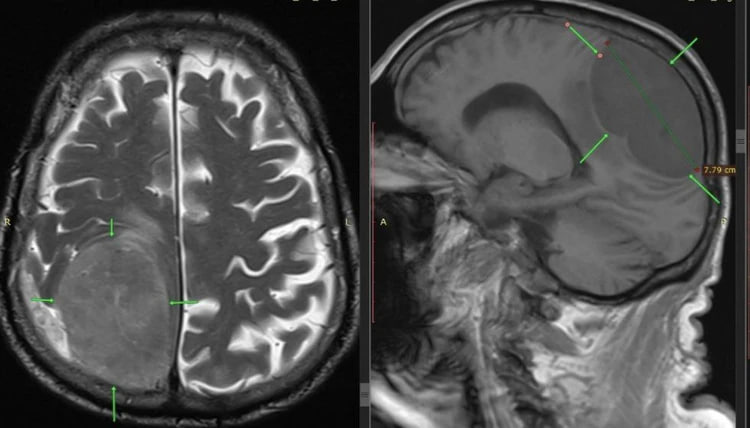

Мужчина попал в больницу, когда у него уже отказала левая нога и левая половина тела. Изначально врачи подозревали инсульт, но все оказалось куда сложнее – в правой теменно-затылочной области мозга нашли опухоль размером 87 см.

Медики начали срочную операцию. Нейрохирурги выполнили трепанацию черепа и полностью удалили опухоль. Сейчас мужчина идет на поправку, и даже движения в левой части тела пришли в норму! Гистология показала, что новообразование доброкачественное.